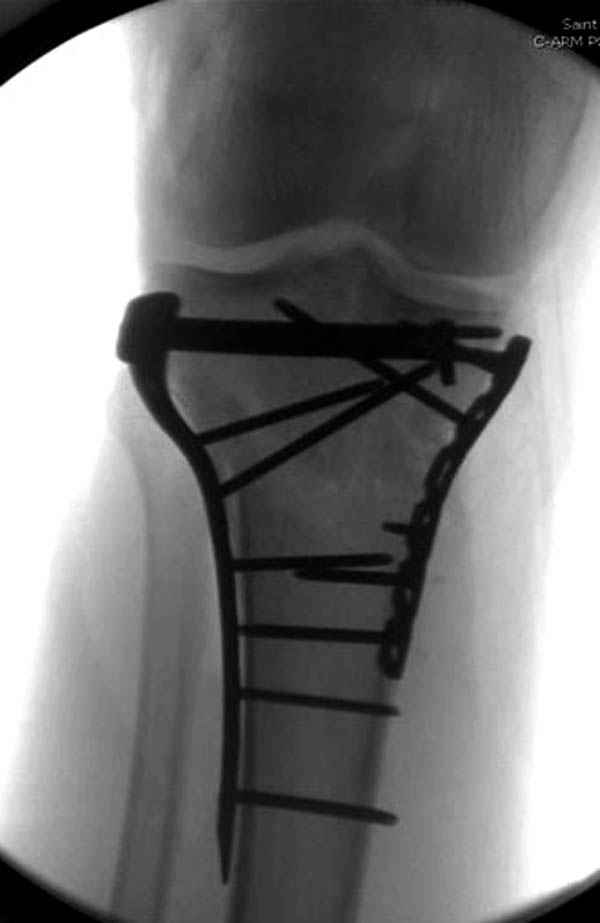

Трудно поверить, что разрекламированная Ортопедическая школа Восточной Украины позволяет такие странные снимки? На прямом снимке сохранен общий контур плато, но не известна судьба импрессии суставной поверхности. На полубоковой?, оставлен без репозиции задне-медиальный отдел, и навряд ли после такой фиксации можно удовлетвориться результатом.

Такая ситуация характерна для многих, когда принимается ошибочное решение, т.е пытаются фиксировать одним имплантом переломы двух мыщелков. Латеральная пластина приемлема только для тех случаев, когда сохраняется интактным медиальный диафизарный кортекс и отсутствует фрагментация на верхушке медиального перелома.

Здесь как раз тот случай, когда результат зависит не только от мастерства хирурга, но и от наличия современных методов исследования. Например, КТ которая поможет рассчитать направления шурупов и установку импланта. Кроме этого, поможет определиться с доступом.